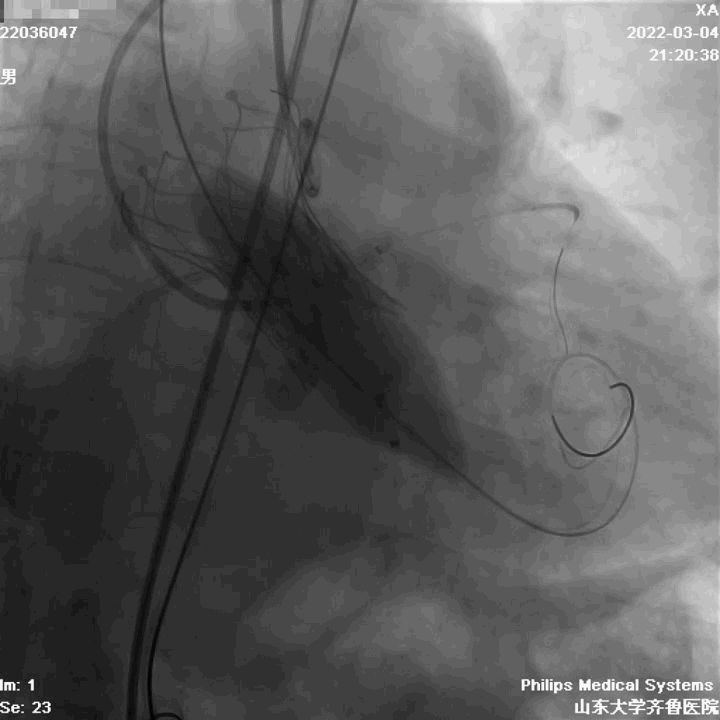

手术过程

定位

起始缓慢释放

造影观察

瓣膜工作,造影观察

完全释放

造影

球囊后扩

最终结果

术中评估球囊扩张效果,放弃已经预装载TAV30瓣膜,植入TAV27型号瓣膜,压差由81mmHg降至5mmHg,EF由38%升至61%。